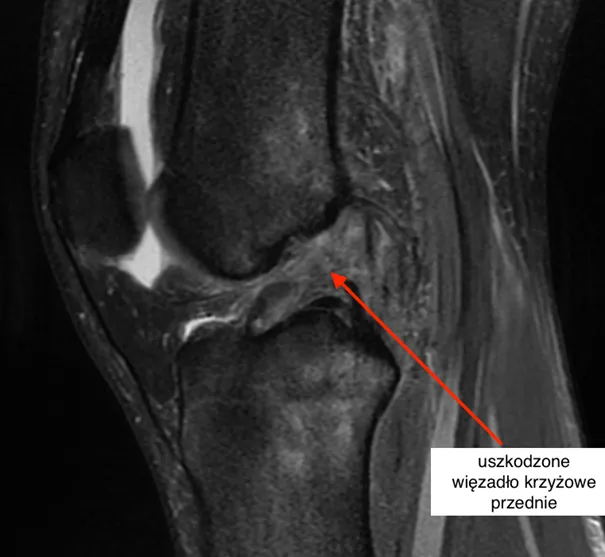

W przypadku umiarkowanego skręcenia (II stopień), gdy więzadła są naderwane, chodzenie może być bardzo bolesne i wymaga odciążenia, a czasami nawet unieruchomienia nogi na okres 4-6 tygodni. Osoby z takim urazem mogą doświadczać znacznego dyskomfortu, co skutkuje ograniczeniem ich zdolności do poruszania się. Natomiast przy ciężkim skręceniu (III stopień), które wiąże się z całkowitym zerwaniem więzadeł, chodzenie jest praktycznie niemożliwe. Taki uraz często wymaga interwencji chirurgicznej oraz dłuższego okresu rehabilitacji, co znacznie wpływa na codzienne życie pacjenta.